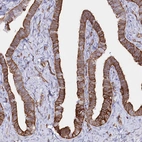

Immunohistochemical staining of human placenta shows strong membranous positivity in trophoblastic cells.